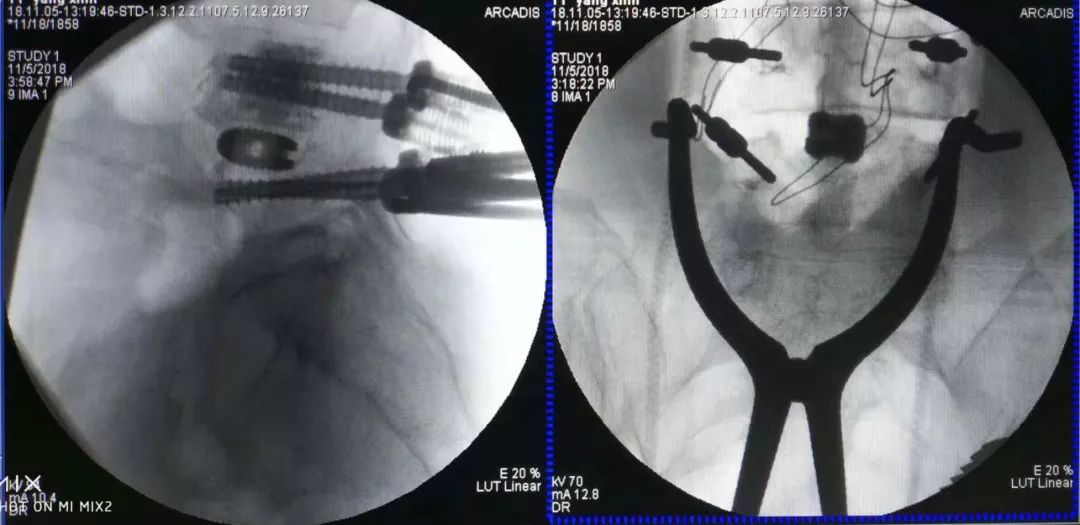

术中情况